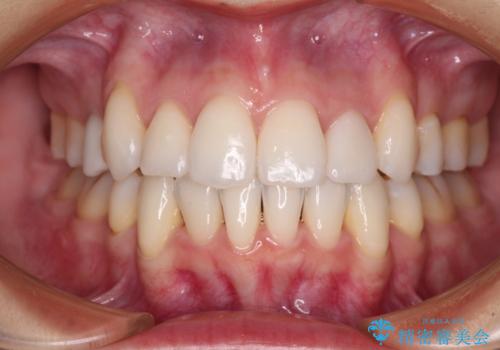

[ 矯正と補綴、総合歯科治療 ] クロスバイトを避ける前歯部審美ブリッジ

![[ 矯正と補綴、総合歯科治療 ] クロスバイトを避ける前歯部審美ブリッジの症例 治療後](https://seimitsushinbi.jp/wp/wp-content/uploads/2021/07/fcd77503a97e2f3a648f6e8698e34626-500x350.jpg?v=1626697051)